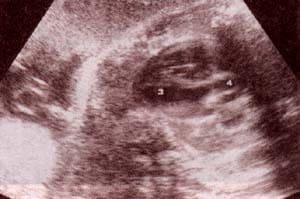

| fig 29.– (a). corazón corte 4 cámaras. proyección apical. 32 semanas. ventrículo izquierdo (1). ventrículo derecho (2). aurícula izquierda (3). aurícula derecha (4). | fig. 29. – (b). proyección subcostal. 36 semanas. ventrículo izquierdo (1). ventrículo derecho (2). aurícula izquierda (3). aurícula derecha (4). |